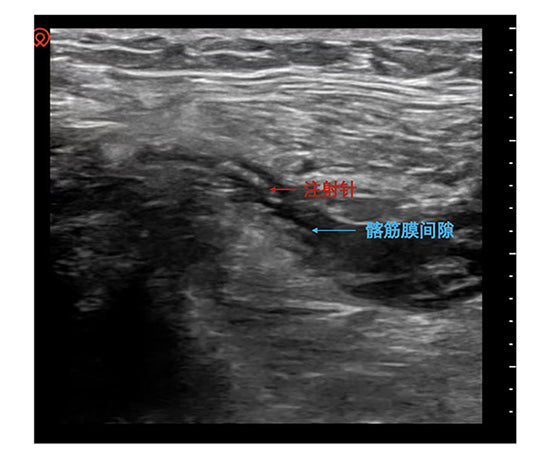

Portable ultrasound enabled visualized precision: tracking the needle path to bypass neurovascular bundles and injecting local anesthetic into the fascia iliaca space. Within minutes, HR and BP returned to baseline.